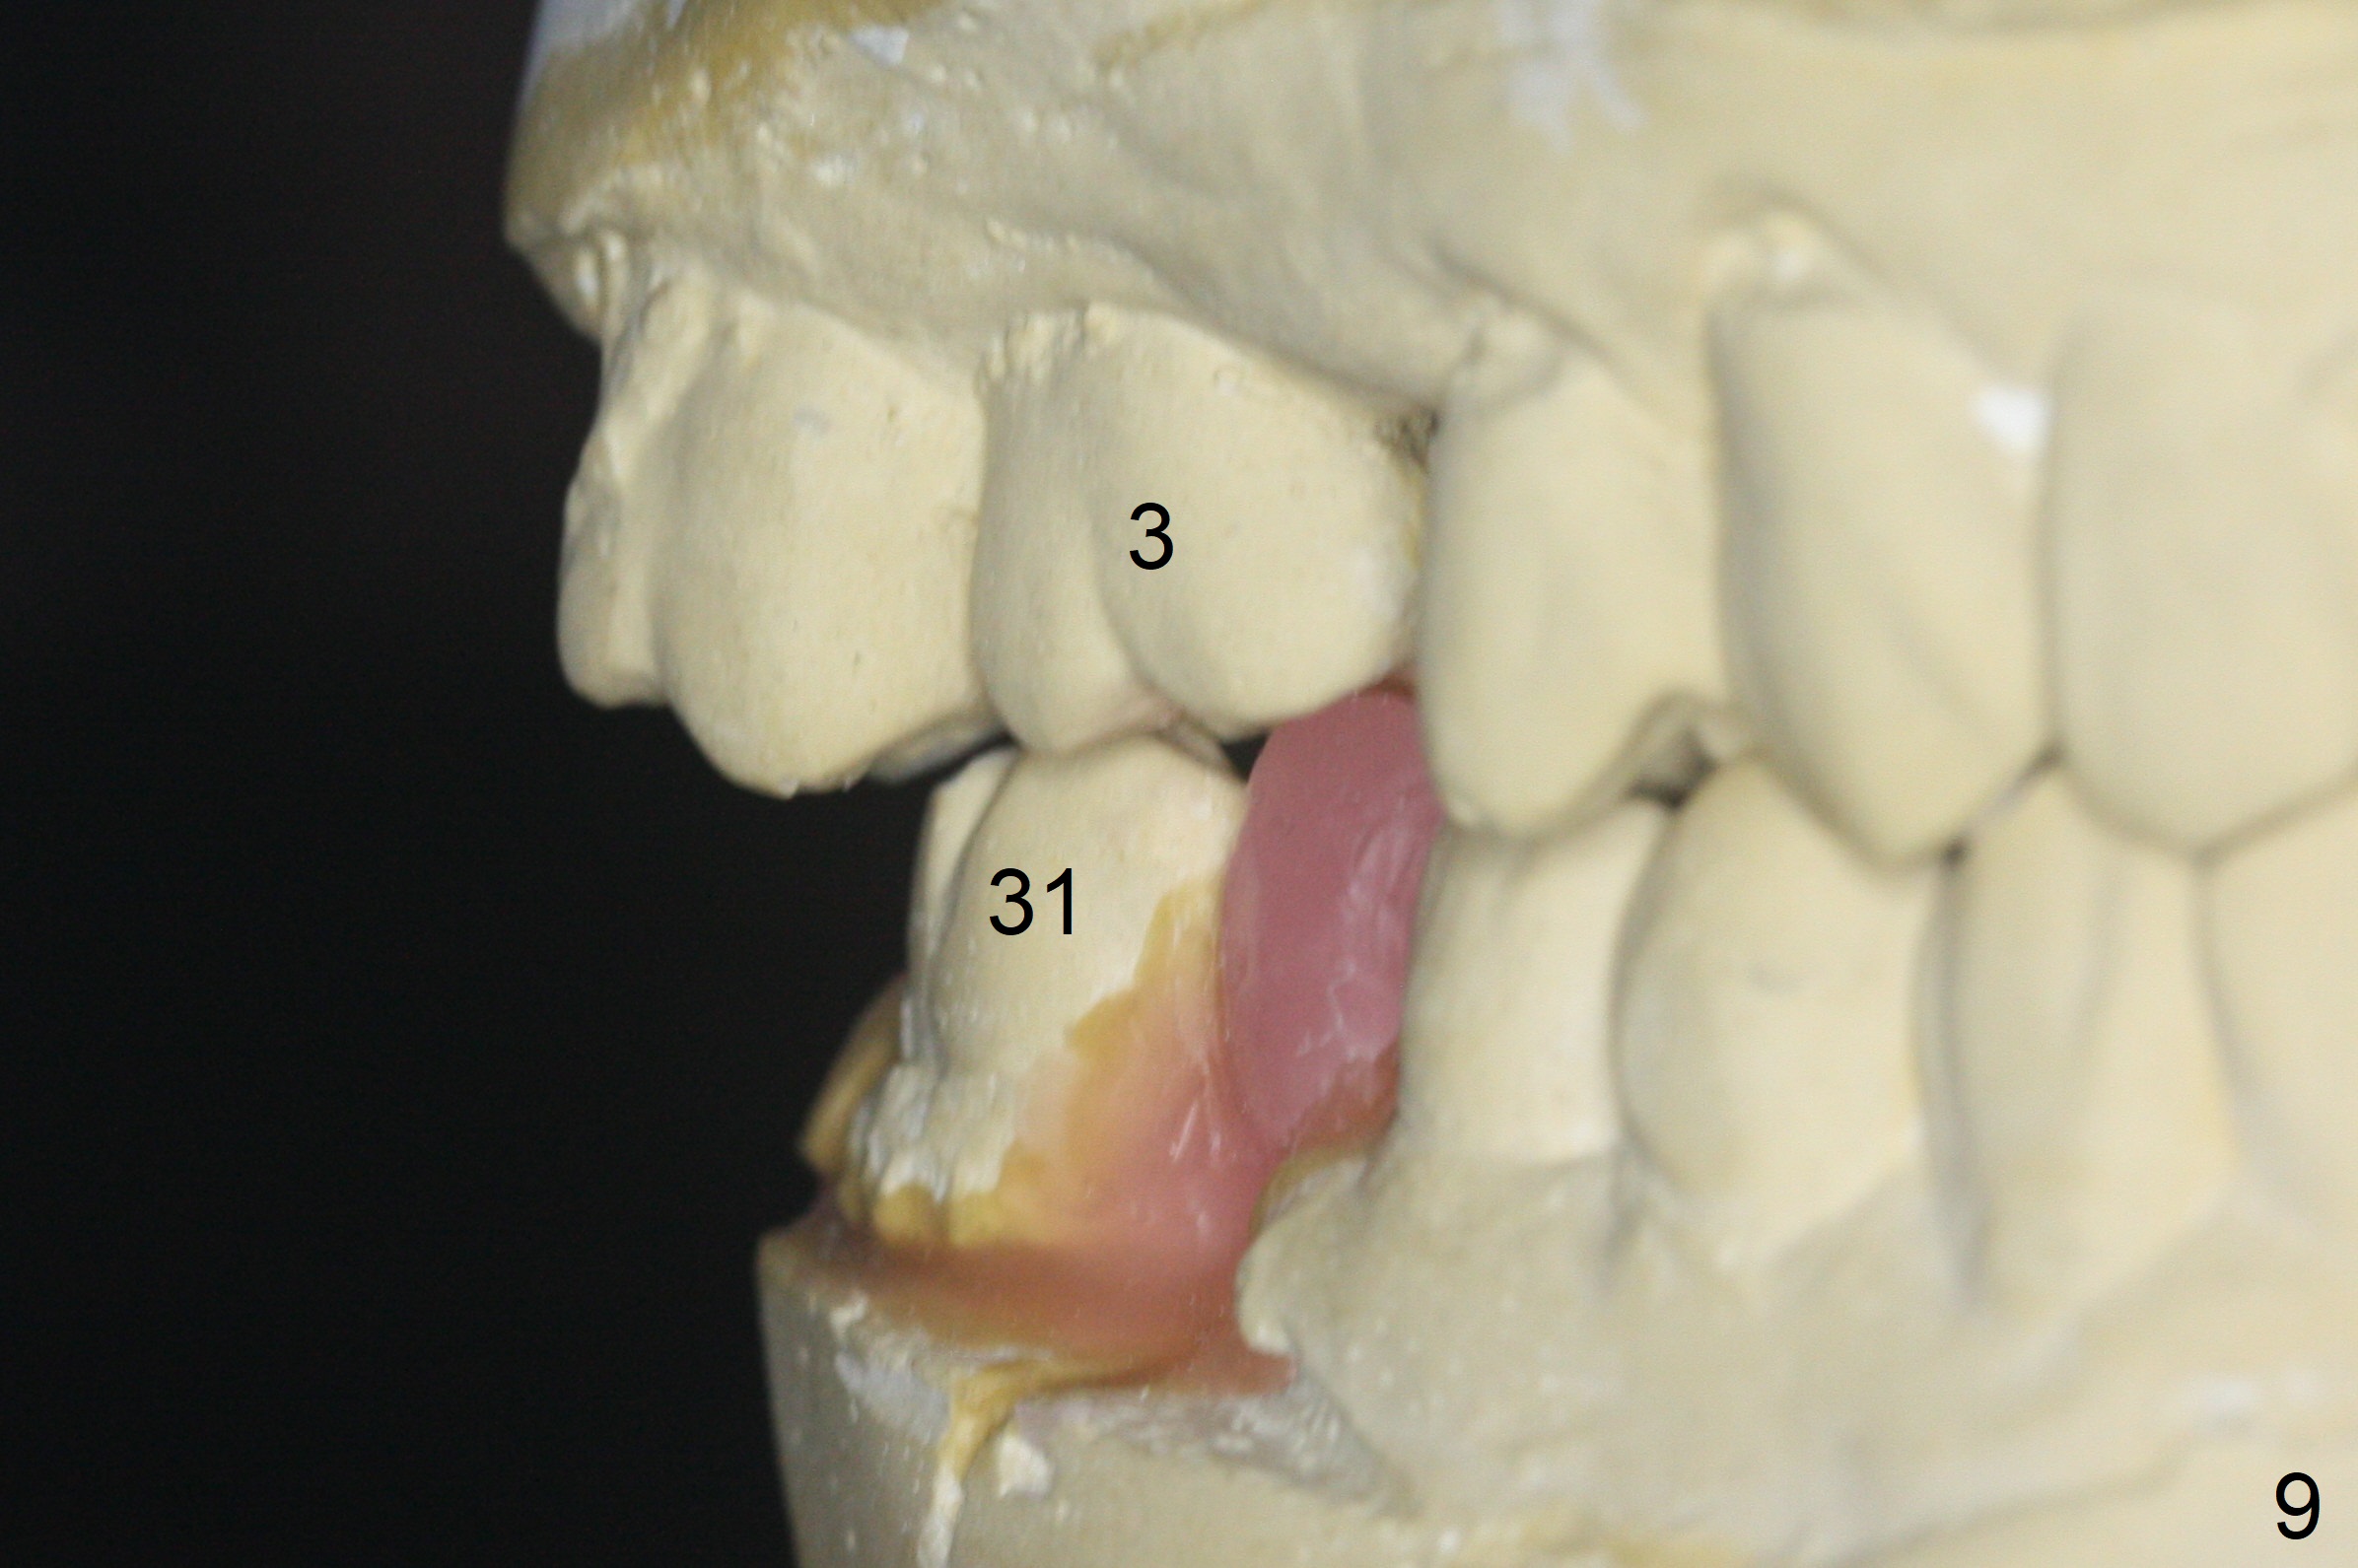

A 64-year-old man has discomfort with the lower left bridge and a loose tooth on the left (Fig.1). It appears that 4 implants are to be placed at #18,19,30 and 31. Since the tooth #4 and 13 are palatalized (Fig.2-4), the teeth #2 and 3 are mesialized (Fig.2 arrow). Besides, the ridge at #30 must be atrophic due to long termed edentulism. A small-diameter implant will be placed at #30 with premolar width (Fig.6-13), while the implant at #31 will be placed distal (arrow, as compared to Fig.2). To establish harmonious occlusion at provisional and final stages, the palatal slope of the mesiopalatal cusp of the tooth #2 will be adjusted (Fig.10).

Prepare 3 large pieces of gauze with the vasoconstrictor. If one of them is still too small for the socket, insert another piece of gauze without the vasoconstrictor for pressure hemostasis. Prepare PRF (x4) and Sinus Master Kit in case short stoppers are needed (Fig.12). CBCT taken immediately preop shows relatively wide ridge at #30 (Fig.14,16). The implant at #31 should be place in the distobuccal aspect of the socket (Fig.15,17): 2 mm drill with 7 mm stopper, 2.8 mm round drill at 5 mm (50 RPM) and 3.6 mm at 3 mm.